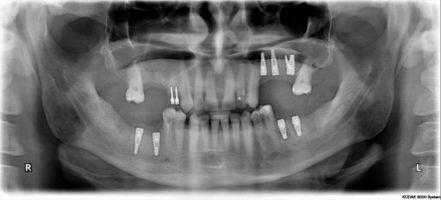

Ортопантомограмма после операции

Ортопантомограмма пациента А. после операции

Ортопантомограмма пациента А. после дентальной имплантации

Ортопонтомограмма пациента Б. пациента до операции

Ортопантомограмма пациента Б. после операции

Ортопантомограмма пациента В. до операции